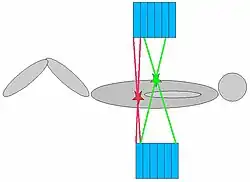

Trifft ein durch Zerfall des Radionuklids entstandenes Positron auf ein Elektron, werden beide vernichtet (Annihilation). Es entstehen zwei Photonen (Gammastrahlung), die sich in einem Winkel von praktisch genau 180° voneinander entfernen. Diese Vernichtungsstrahlung trifft gleichzeitig (koinzident) zwei Detektoren. Dadurch kann auf rechnerischem Wege durch Einsatz eines Computers der Ort der Positronenemission eingegrenzt werden. Werden in zwei Detektoren γ-Quanten der richtigen Energie zeitgleich nachgewiesen, wird dies als Positron-Elektron-Vernichtung an einem Punkt auf der Linie zwischen den beiden Detektoren interpretiert (sogenannte Line Of Response (LOR) bzw. Koinzidenzlinie). Die Technik der Positronen-Emissions-Tomographie zielt darauf ab, eine möglichst hohe Rate echter solcher Ereignisse zu detektieren und gleichzeitig die Rate von Fehldetektionen niedrig zu halten.

Ähnlich wie bei der Szintigrafie wird dem Patienten zu Beginn einer PET-Untersuchung ein Radiopharmakon verabreicht, meist durch Injektion in eine Armvene. Die PET verwendet Radionuklide, die Positronen emittieren (β+-Strahlung). Bei der Wechselwirkung eines Positrons mit einem Elektron im Körper werden zwei hochenergetische Photonen einer Energie von je 511 keV (entspricht der Frequenz 123 EHz und der Wellenlänge 2,43 pm) in entgegengesetzte Richtungen, also mit dem Winkel 180 Grad zueinander, ausgesandt (Vernichtungsstrahlung). Das PET-Gerät enthält viele ringförmig um den Patienten angeordnete Detektoren für die Photonen. Das Prinzip der PET-Untersuchung besteht darin, Koinzidenzen zwischen je zwei gegenüberliegenden Detektoren aufzuzeichnen. Typische Zeitfenster der Nachweiselektronik betragen hierfür 4,5 bis 15 Nanosekunden. Aus der zeitlichen und räumlichen Verteilung dieser registrierten Zerfallsereignisse wird auf die räumliche Verteilung des Radiopharmakons im Körperinneren geschlossen und eine Serie von Schnittbildern errechnet. Häufige Anwendung findet die PET bei stoffwechselbezogenen Fragestellungen in der Onkologie, Neurologie sowie Kardiologie.

Wahre Koinzidenzen („Trues“)

Ziel der PET ist es, ausschließlich „Trues“ zu messen. Ein True liegt vor, wenn zwei entstandene Photonen das Untersuchungsvolumen ohne Wechselwirkung (Streuung) durchqueren konnten und ihre volle Energie in den Detektoren deponiert haben, die im Anschluss von der Messelektronik auch erkannt wurden. Die Voraussetzungen, dass ein True gemessen werden kann, sind:

- Die Flugrichtung beider Photonen liegt im Sichtbereich der Detektoren.

- Keines der Photonen hat durch Streuung (im Patienten) zu viel Energie verloren, so dass beide nachgewiesen werden.

- Keines der Photonen ist durch Absorption verschwunden.

Man stelle sich eine Nuklidanreicherung vor, die sich in der Nähe eines wassergefüllten Zylinders mit 30 cm Durchmesser befindet. Die dort zerfallenen Nuklide senden ihre Vernichtungsstrahlung in alle Raumrichtungen aus. Es sollen zwei Fälle betrachtet werden: Fall 1: Die beiden entstandenen Photonen 1 und 2 fliegen exakt tangential von der Objektoberfläche weg (violette Pfeile), weder Photon 1 noch Photon 2 durchdringt irgendeinen Teil des Zylinders. Fall 2: Photon 1 zielt radial in Richtung Zylindermitte. Naturgemäß entfernt sich Photon 2 vom Zylinder, ohne auch nur einen Teil des Zylinders zu durchdringen (nach oben weisender roter Pfeil). Die Wahrscheinlichkeit ist groß, dass Photon 1 beim Durchlauf von 30 cm Wasser absorbiert und damit Photon 2 zu einem „Single“ wird und damit für die Bildrekonstruktion nicht mehr zur Verfügung steht.

Würde die Absorption der Strahlung bei der Bildrekonstruktion unberücksichtigt gelassen, wären Artefakte die Folge; die gemessene Aktivitätsverteilung stimmte ohne Absorptionskorrektur nicht mit der tatsächlichen Verteilung überein.

Relevanz für die Quantifizierung von Anreicherungen

Die Wahrscheinlichkeit einer Absorption ist im Fall 2 (rote Pfeile) unabhängig davon, ob die Annihilation an der Oberfläche (Ort A) oder in der Mitte des Objektes (Ort B) stattfand. Bei Annihilation an der Oberfläche (Ort A) durchläuft Photon 1 den gesamten Zylinder, Photon 2 nur Luft, bei Annihilation in der Zylindermitte (Ort B) durchlaufen beide Photonen den halben Zylinder, was zur selben Absorptionswahrscheinlichkeit führt. Da die Absorptionswahrscheinlichkeit somit nur von der Gesamtschwächung des durchstrahlten Volumens, nicht jedoch vom Ort der Annihilation auf der Koinzidenzlinie abhängt, ermöglicht dies eine tiefenunabhängige Quantifizierung der Nuklidanreicherung.